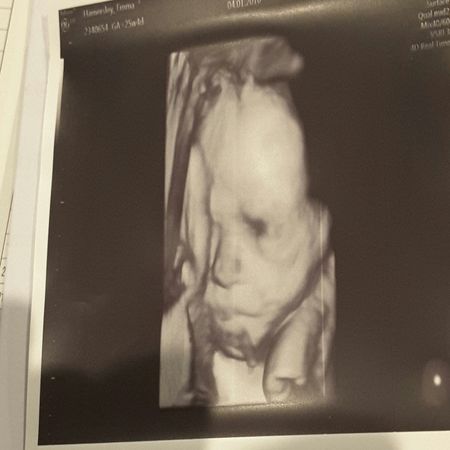

Hi All My head is still spinning. 2.5 weeks ago I was a busy mum to 2 under school age boys, working part-time, and halfway through my third pregnancy. Now I have had a mastectomy, partial auxiliary node clearance, a fairly scary diagnosis, had to change obs and maternity hospitals and I now have more doctors and specialists than I do fingers??. The last two years have been hell enough losing my mum to leukemia at just 57, then my darling nan a couple months later only to be followed by my 1.5 yr old niece to be diagnosed with leukemia also - fingers crossed she gets the all clear. .. just waiting on final results afer bone marrow transplant) - and now this! However bub is unfazed by any of this and is coming along just fine. I'm nervous about starting chemo with him still on board but I'm assured he will be fine. Anyway after all this "action" it was reassuring to see his "face" - made me cry but happy tears for a change. Here's the sneak peak I got. Thanks for the vent! Emma xx24Views0likes6CommentsWhat to do?!!